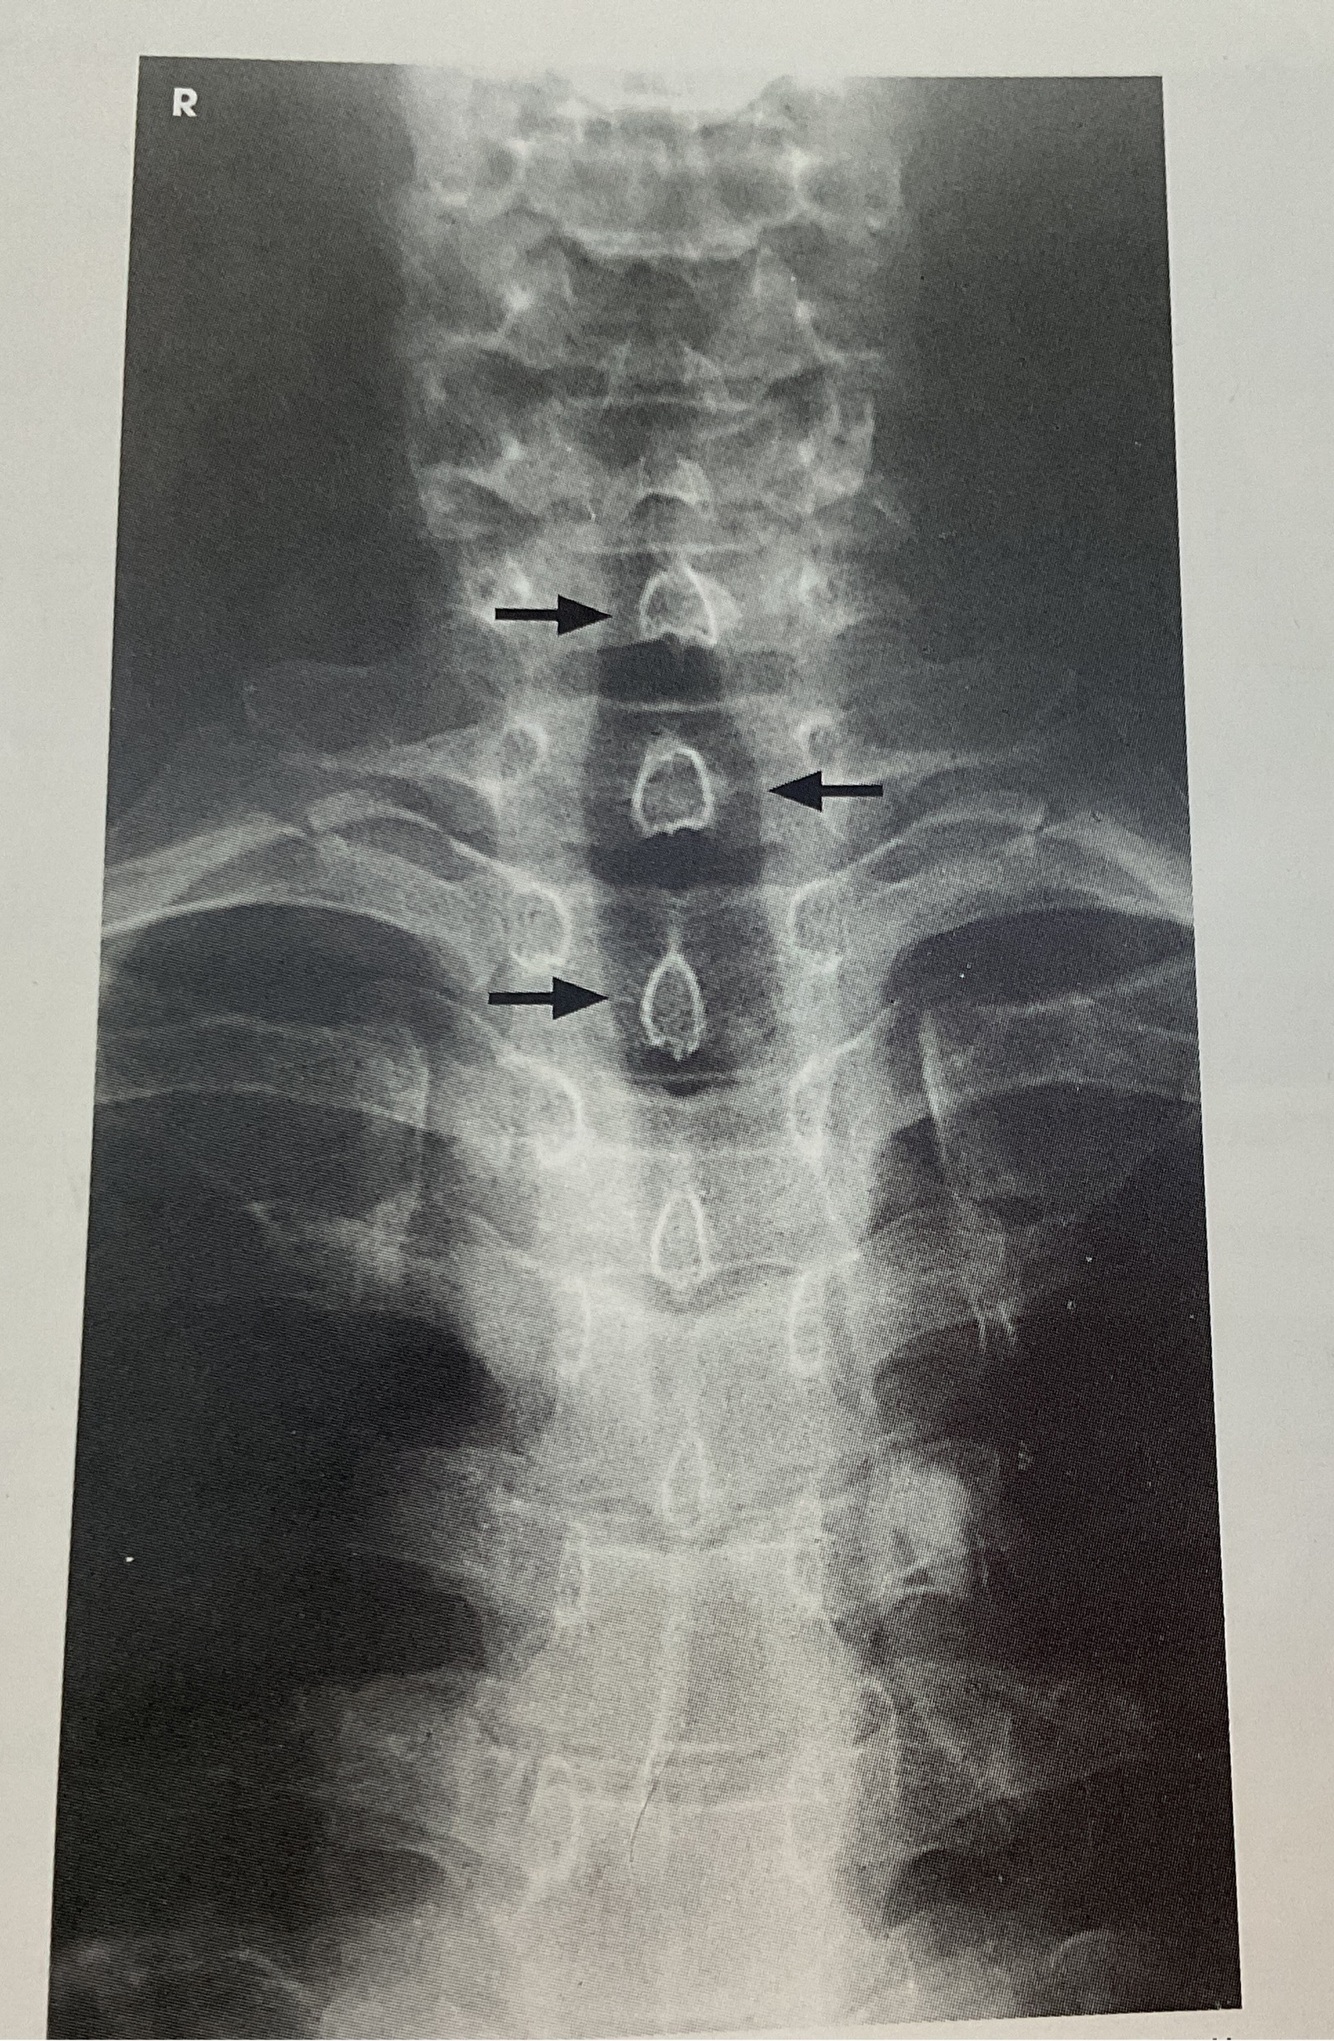

3 Evaluation for Soft Tissue Neck

AP Projection

A

~ Air Filled Upper Airway from Pharynx to Proximal. trachea (UPPER AIRWAY)

~ AIr filled airway from midcervical to midthoracic region (TRACHEA & SUPERIOR MEDIASTINUM)

~NO. ROTATION w/Spinous processes equidistant to pedicles & aligned w midline of cervical bodies